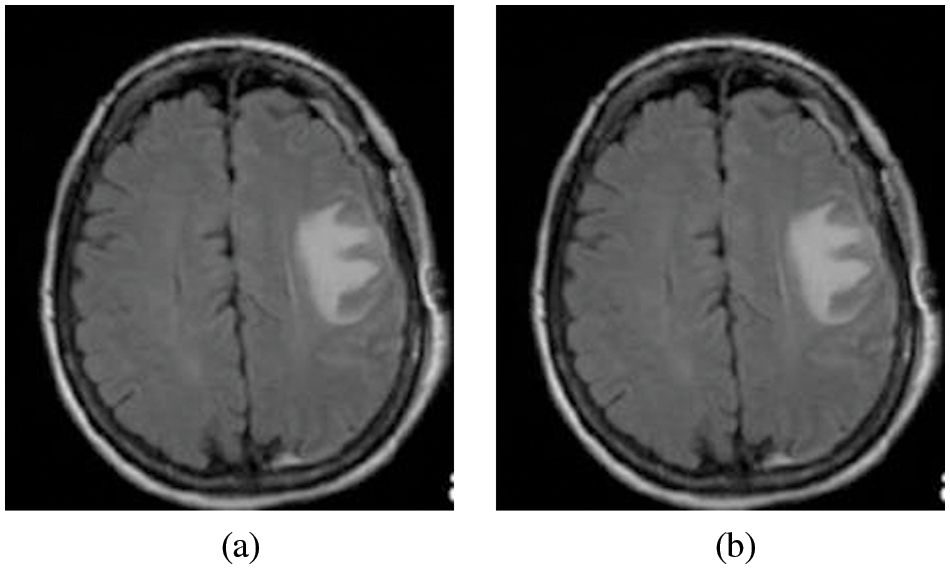

Eq. (3) is used to calculate the median value by restoring the gray level of every pixel by the median of the gray levels in a region of the pixels, in its place of using the average operation. Fig. 3a the Original image input image for the system and Fig. 3b is the Pre-Processed image as the output of the process

Figure 3: (a) Original image and (b) Pre-processed image